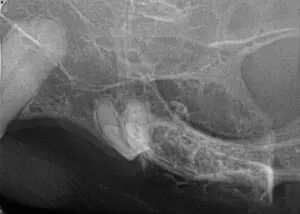

Diagnostic radiographs were taken (see below). What do you see?

There is bone proliferation/expansion in the 208/209 area. Visible tooth resorption (type I) is noted on 208.